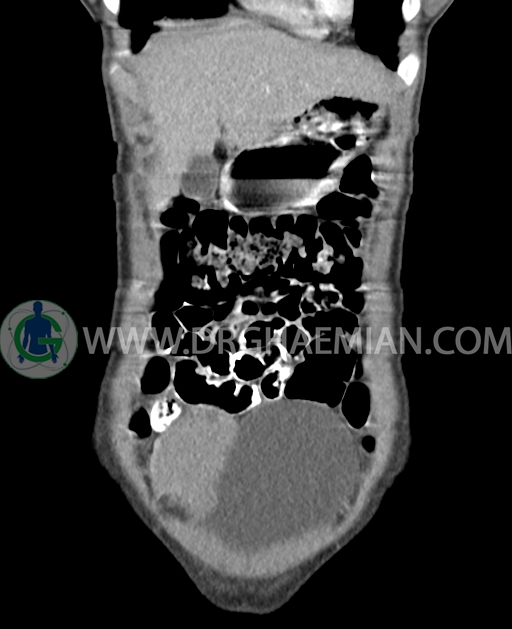

سی تی اسکن شکم و لگن از تشعشعات برای ایجاد تصاویر عرضی مقطعی از نایحه شکم و بین استخوان های لگن استفاده می کند. در این کیس تومور سلول زایا به ابعاد mm 125 x 112 x 80 دیده می شود.

در سی تی اسکن اسپیرال شکم و لگن با کنتراست خوراکی و وریدی (مولتی دیدکتور 16 با مقاطع ظریف و بازسازی های ساژیتال و کرونال) :

توده هیپردنس لوبوله بزرگ به ابعاد 125x112x80mm حاوی نواحی سیستیک داخلی و enhancement قابل توجه پریفرال همراه با آسیت متوسط در فضای شکم و لگن با احتمال بیشتر با منشا از تخمدان راست، درون لگن دیده می شود که در درجه اول مطرح کننده germ cell tumor می باشد .